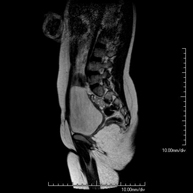

- Lumbar spine MRI

This non-invasive diagnostic procedure uses an electromagnetic field and radio waves (from a transmitter and receiver) to acquire high-definition anatomical images of the lumbar and sacral regions. It is a radiation-free procedure. Indicated for: trauma, sciatica, herniated discs, tumours, infections.

- Thoracic + lumbar spine MRI

A non-invasive diagnostic test that involves obtaining high-definition anatomical images of the thoracic and lumbar spine using an electromagnetic field and radio waves (with transmitter and receiver). It is a radiation-free procedure. Indicated for: trauma, spinal degeneration, hernias.